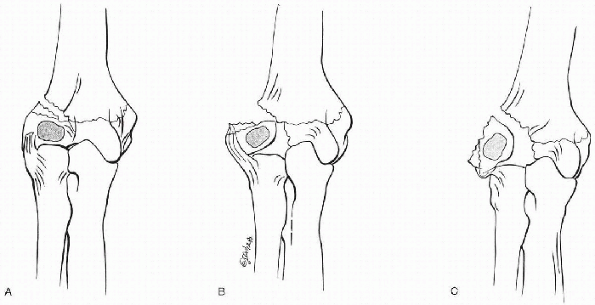

![]() |

Figure 12.3-4 Classification of lateral condyle fractures. (A) Milch type I, lateral view (Salter-Harris type IV). (B) Milch type II, lateral view (Salter-Harris type II).

The commonest fracture line travels from

trochlea (Milch type II) (Fig.12.3-4). -

The rare fracture line type starts from

the posterolateral metaphysis, through the physis and body of the

Figure 12.3-5 Rutherford classification of lateral condyle. (A) Type I. (B) Type II. (C) Type III.